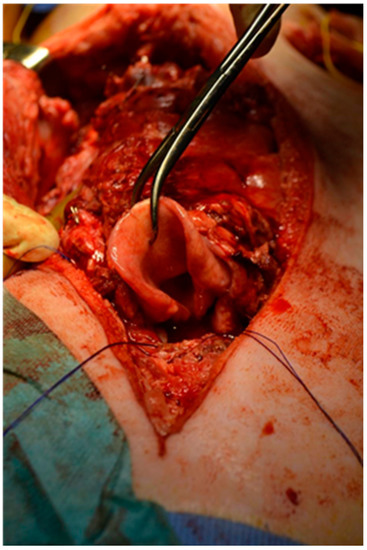

2.3. Preparation of the Recipient

2.4. Transplantation